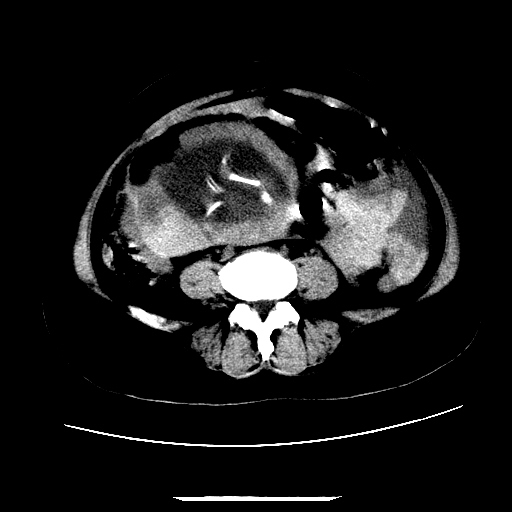

f,45y.怀孕4月晕倒,b超提示死胎,有手术结果,请展开讨论后明天告诉。

膈下-肠间隙内见气体密度影,子宫轮廓显示不清,宫腔-腹腔积液,首选考虑---子宫破裂出血。

1)宫腔妊娠。2)子宫破裂出血,腹腔及盆腔积血。

感谢同行们的高见。手术结果:子宫破裂出血。

我们的诊断是:腹、盆腔积液(考虑腹盆腔脏器破裂出血);宫腔妊娠。让人纳闷的是当时我们没有经验,现在回头看看分析:4月宫腔妊娠:1、洋膜囊不可能紧贴胎体这么小;2仔细看看子宫后壁肌层模糊不清;3腹、盆腔液体来源原因?4、45岁高龄妊娠有晕倒。由此可大胆诊断:宫腔妊娠子宫破裂出血。